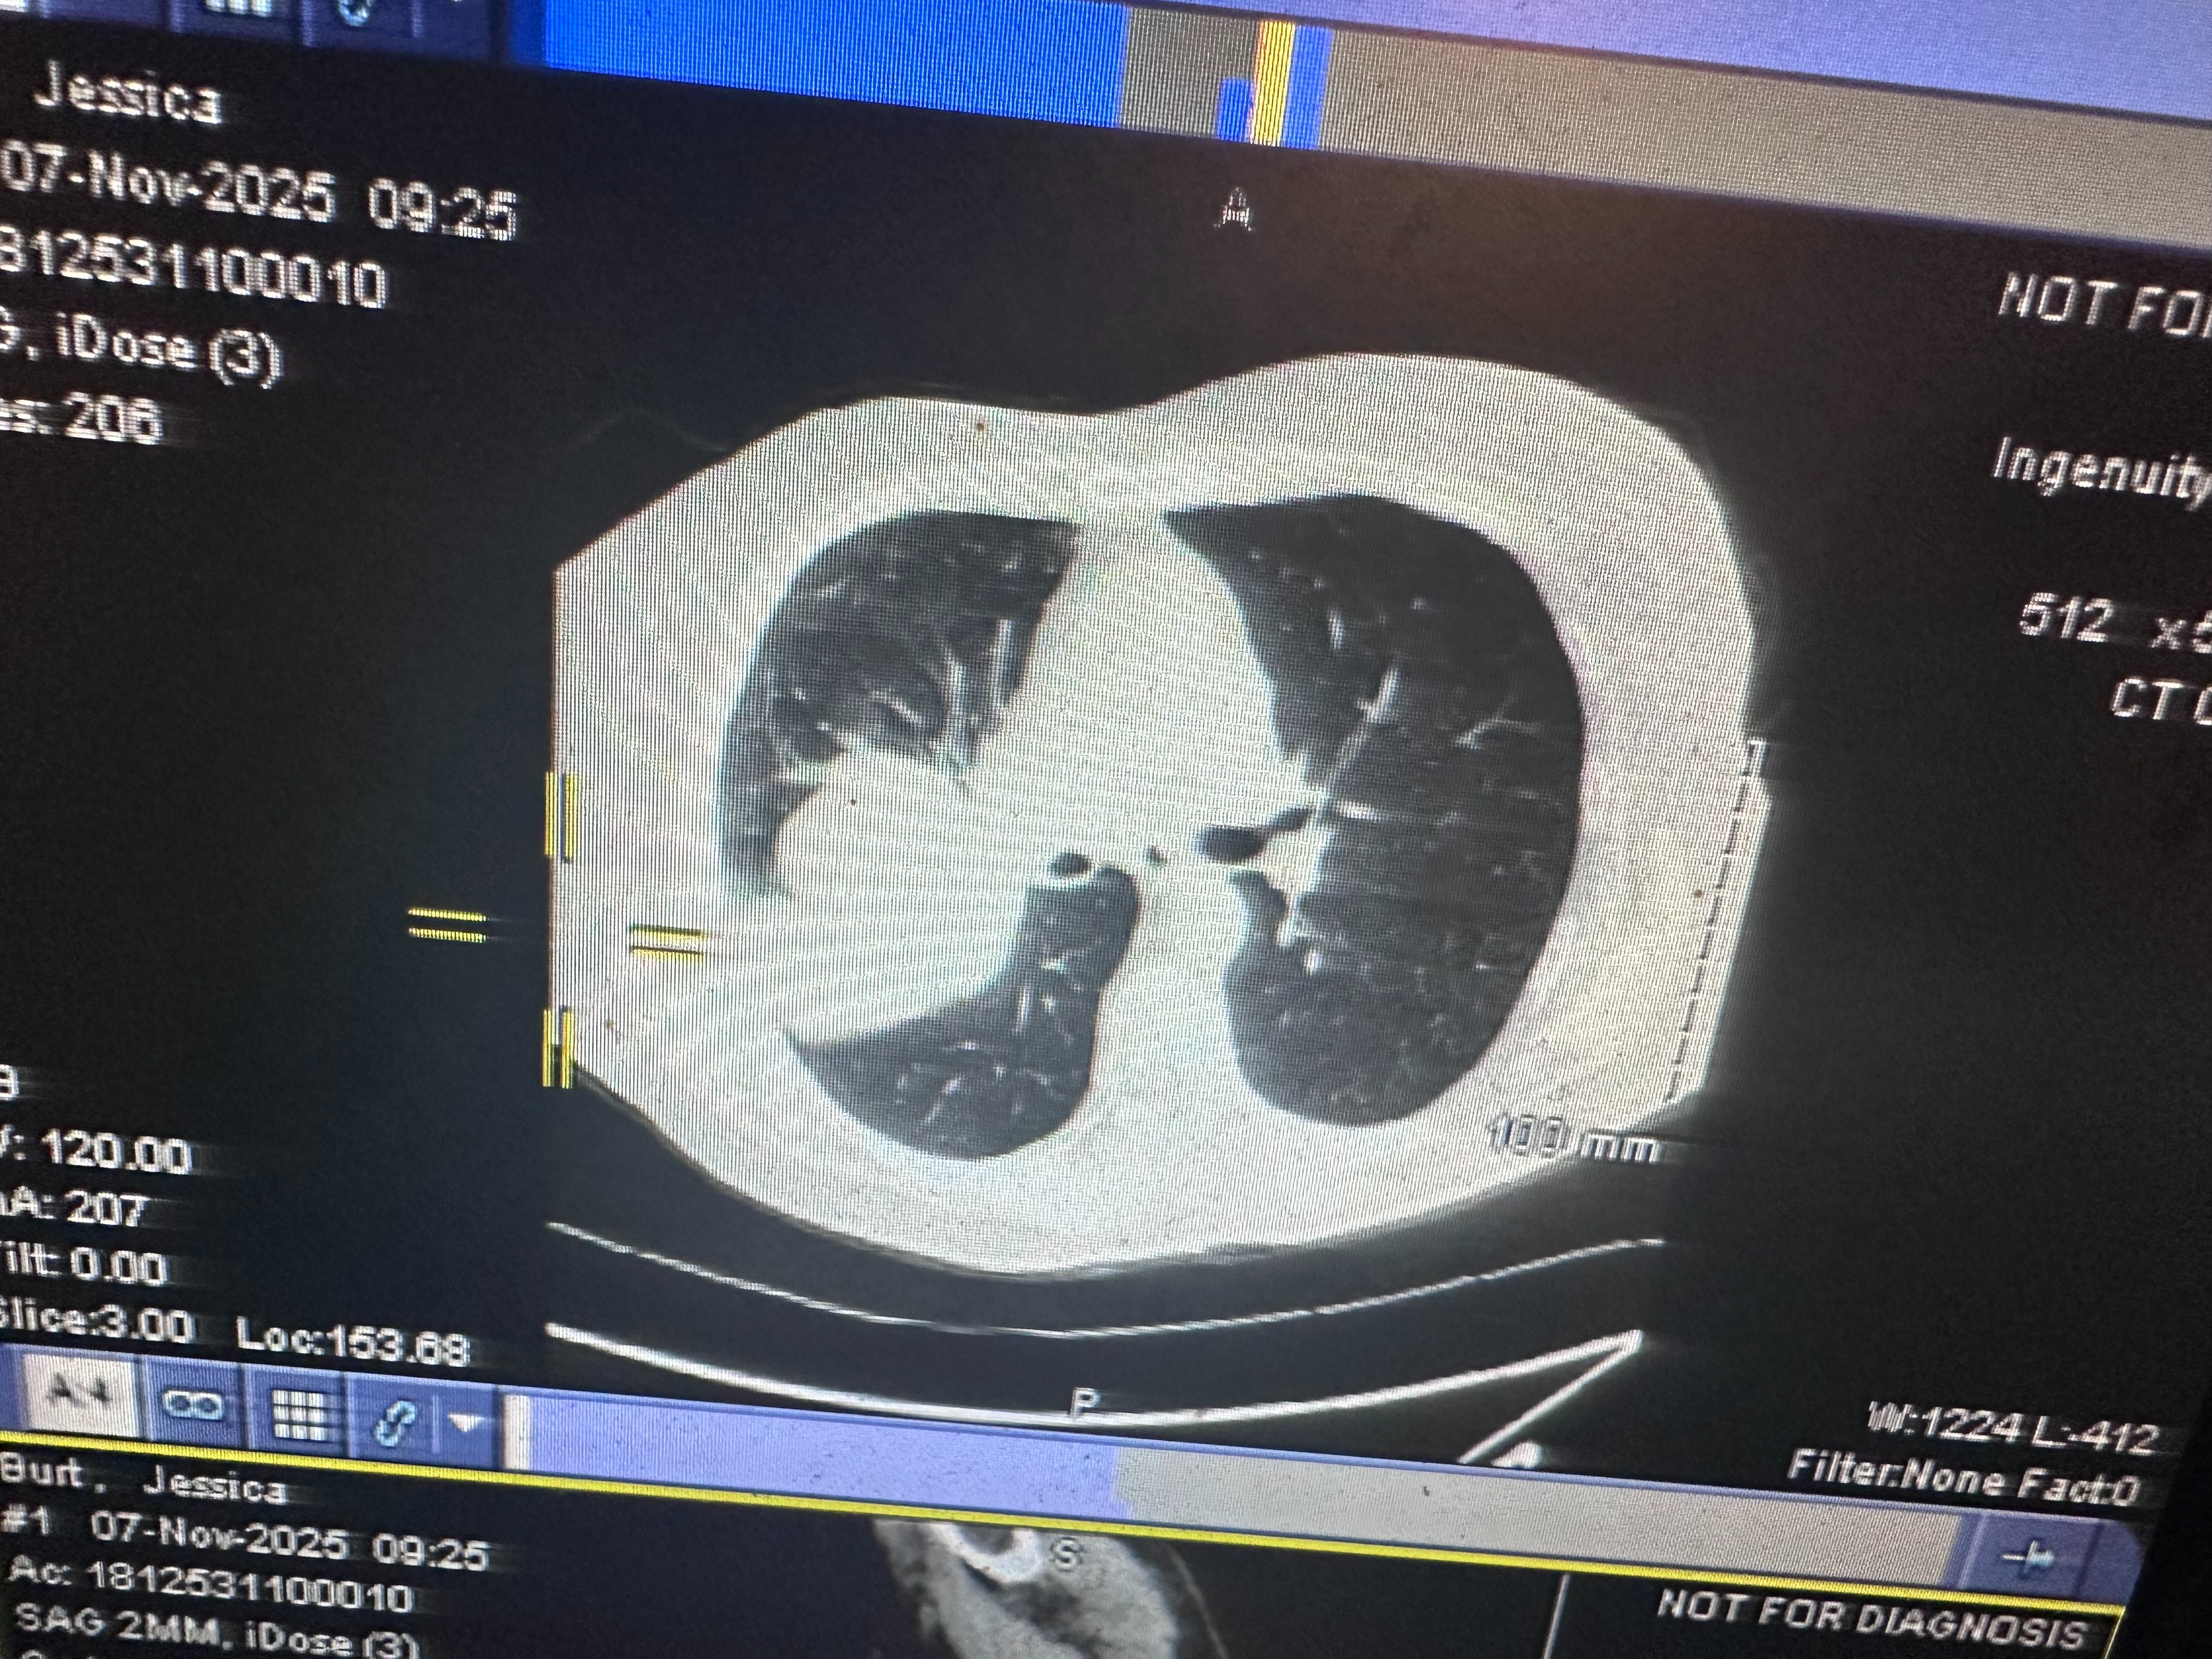

In early October, she lost her father on October 1st, and was still grieving that loss when, later that same month, our world was turned upside down again. In late October, she was diagnosed with stage 4 lung cancer. We’re still waiting for more test results and treatment options, but that day changed everything. I’ll never forget the family meeting when my parents told us — how my dad held her hand at the table, both of them trying to stay strong for us even as the room went silent with shock and heartbreak.